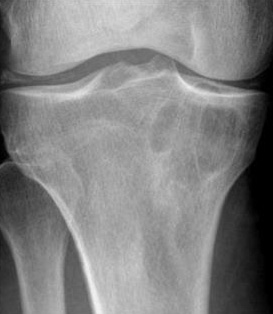

Intraosseous ganglion

It is a subarticular lytic lesion containing synovial fluid and is often associated with degenerative joint disease. It is encountered in the proximal and distal ends of tibia. Medial malleolus is common site (Figure 19).

Figure 19: Intraosseous ganglion in the medial condyle of tibia.